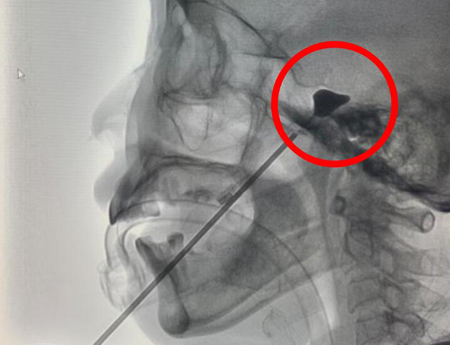

右侧面颊部穿刺后球囊压迫右侧三叉神经半月节,形成理想球囊形状

这个手术,仅需要在面部右侧口角出开微小穿刺点,属于微创手术。手术通过一个鞘管在X线透视监视下,将一个球囊导入Meckle’s腔的三叉神经的半月节,然后缓慢注入对比造影剂充盈球囊,把导致三叉神经痛的神经纤维解除卡压,并通过扩张的微球囊压迫破坏,从而对三叉神经痛进行治疗。在陈女士的手术中右侧面颊部穿刺后球囊压迫右侧三叉神经半月节,上图为术中理想球囊形状。同时,手术时间非常短,仅用15分钟就顺利结束。